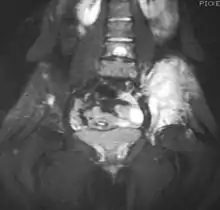

Magnetic resonance imaging (MRI) should be routinely used in the work-up of malignant tumors. It will show the full bony and soft tissue extent and relate the tumor to other nearby anatomic structures (e.g. vessels). Gadolinium contrast is not necessary as it does not give additional information over noncontrast studies, though some current researchers argue that dynamic, contrast-enhanced MRI may help determine the amount of necrosis within the tumor, thus help in determining response to treatment prior to surgery.[25]

Computed axial tomography (CT) can also be used to define the extraosseous extent of the tumor, especially in the skull, spine, ribs, and pelvis. Both CT and MRI can be used to follow response to radiation and/or chemotherapy. Bone scintigraphy can also be used to follow tumor response to therapy.[26]